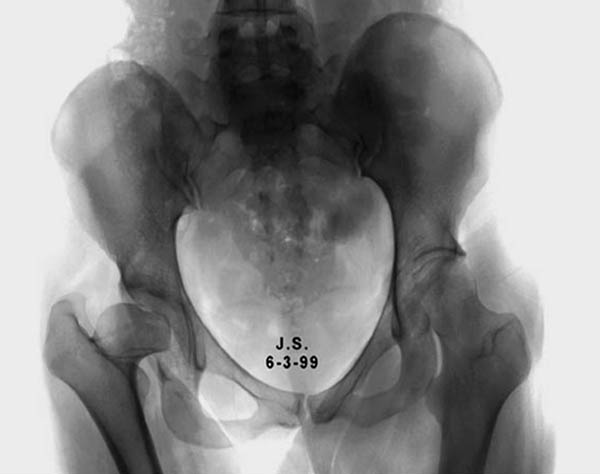

Здесь комбинированная патология тазобедреннего сустава, связанная с высокостоящим вертелом и отсутствием (ротирована?) шейкой. А на стороне вертлужной впадины диспластический сустав. Обычно высоко расположенный вертел приводит к уменьшению силы мышц абдукторов, но отстутствие шейки привело к вертикальному расположению  сил в суставе. Боли появляются из-за вертикального давления, а неровные контуры головки приводят к ограничению движений в суставе. Такое состояние быстро изнашивает сустав, и больные в молодом возрасте заканчивают тотальным протезированием.

Протезировать может любой специалист по артропластике, но все таки молодой возраст, не очень приятная перспектива. Желательно сохранить собственный сустав и иногда  укорочение конечности можно устранить за счет удлинения шейки, а в дальнейшем Периацетабулярная Остеотомия. Но, еще раз повторяю, иногда!

Для оценки пригодности сустава надо сделать снимки во внутренной и наружной ротации, а также с отведением и приведением каждого сустава. Сравнительные снимки  покажут возможный подвывих и укорочение, а также состояние суставной щели. 3D Компьютерная Томография покажет возможную ротацию шейки.

Представленный случай имеет схожесть....,  и последний снимок после 2 х лет.